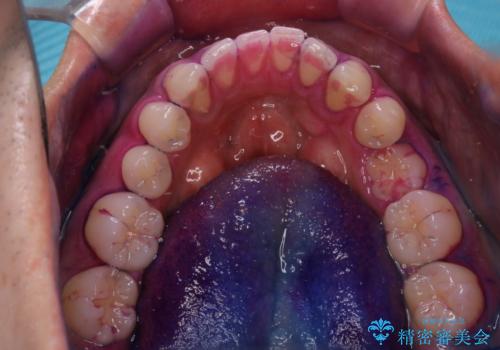

親知らずを抜いて1週間後にPMTC 歯のクリーニング

- 親知らずの抜歯後の約1週間後に抜糸(縫った部分の糸とり)で来院されました。その際、抜歯後は傷口が怖くて歯磨きが上手くできず、汚れや口臭が気になるためクリーニングも希望されました。

抜歯後は多少出血したり、違和感や痛みを感じたりすることがあります。そのため親知らずを抜いたり、外科的な処置をするといつも通りの歯磨きがしづらくなります。また、傷口の周りが心配で、歯ブラシをするのが怖くなるものです。抜歯後落ち着いたら、歯科医院にて専門の機械を使用しクリーニングをすることがおすすめです。抜歯前や後にPMTCを行うことで、お口の中の健康維持につながり、その後の感染・腫れ・口臭予防などになります。

親知らず抜歯後正常に治癒が進んでいれば1週間後から可能です。